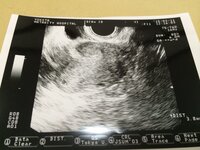

妊娠 現在、妊娠9wです。 2回目の検診に行ったら、いきなり"双子"だと言われ、ただただビックリして帰ってきました。その時先生に一卵性か二卵性か聞けば良かったのですが、そんな余裕もなく、今になってQ 双子エコー写真から一卵性、二卵性わかります? 現在、妊娠9wです。 2回目の検診Aug 05, · 双子には、1つの卵子に1つの精子が受精した受精卵が、なんらかのきっかけで2つに分かれてそれぞれに成長する「一卵性」と、2つの卵子が2つの精子それぞれと受精して成長する「二卵性」があります。一卵性の場合は、おなかの赤ちゃんは同性。二卵性のSep 03, 10 · 一卵性双子のエコー写真 テーマ: ブログ 今日急に思い立って、双子を妊娠していた頃のエコー写真を引っ張り出して見てみました。 久しぶりに見てみると、妊娠当時と変わらず愛おしくて優しい気持ちになりました。 めーとゆーが私のお腹にいた証で

二卵性双子の原因:高齢妊娠、卵巣機能低下 nabana双子妊娠中のブログ 21年06月07日 1549 双子(二卵性)を授かることができて、奇跡だ~としか思わなかったけど、医学的原因を知りたくなって自分なりに調べてみた(間違ってたら、ごめんなさい)二卵性Nov 07, 16 · 妊娠6~7週になり、1つの胎嚢の中に心臓が2つ確認できると、双子であることが判明します。 ただ、前述の通り、エコーの角度によっては心臓が2つ確認できないこともあります。Jun 04, 21 · 答えとしては、 「2人同時のエコー写真がもらえたのは9週前後まで」 です。 ママ それ以上大きくなるとおさまりきらないし、1人1人丁寧にみていくから個別のエコーになるんだよ。 今回はそんな双子のエコー写真を、 双子妊娠が判明した5週目から29週

双子の妊娠はいつわかるの? 双子を妊娠しているかどうかは妊娠初期の超音波検査でわかります。 妊娠5週目頃には胎嚢が確認できるので、もともと2つの受精卵から生まれた二卵性双胎であれば胎嚢が2つ見つかります。 一方、一卵性双胎の約70〜75%はJul 26, 19 · 双子妊娠13週 エコー検査 クリニックではなく、病院のエコー検査へ。 みかんちゃんは口がパクパクしていて、りんごちゃんは手を振っている感じでした。 これが13週の双子のエコー写真 写真上の方に、りんごちゃんの手が認識できるでしょうか。Nov 07, 17 · 二卵性双生児 二卵性の双子は、受精卵が2つある状態なので、胎嚢も2つあります。そのため妊娠するとすぐに分かります。 妊娠3週から5週までに分かることが多いと言われています。 一卵性

双子はいつわかる?判明は遅い?エコーで一卵性・二卵性は 妊娠 6週~7週頃のエコー検査 では胎芽と心拍が確認できるようになります。 ここで、1人の妊娠と双子の妊娠ではわかるまでにどれくらいの差があるのかみていきましょう。Mar 23, 21 · 双子妊娠13週 エコー検査 クリニックではなく、病院のエコー検査へ。 みかんちゃんは口がパクパクしていて、りんごちゃんは手を振っている感じでした。 これが13週の双子のエコー写真 写真上の方に、りんごちゃんの手が認識できるでしょうか。一卵性双子妊娠12wです。 今日エコー写真妊娠週 7w3d 4wの写真の時は双子だと言われておりましたが、今回心音も確認でき、三つ子だということが判明しました ( ( ( (;゜Д゜)))))))大きさは6wぐらいの小ささみたいですが、3人とも元気に心臓が動いてくれていました! おなまえ あつまむ ねんれい 27